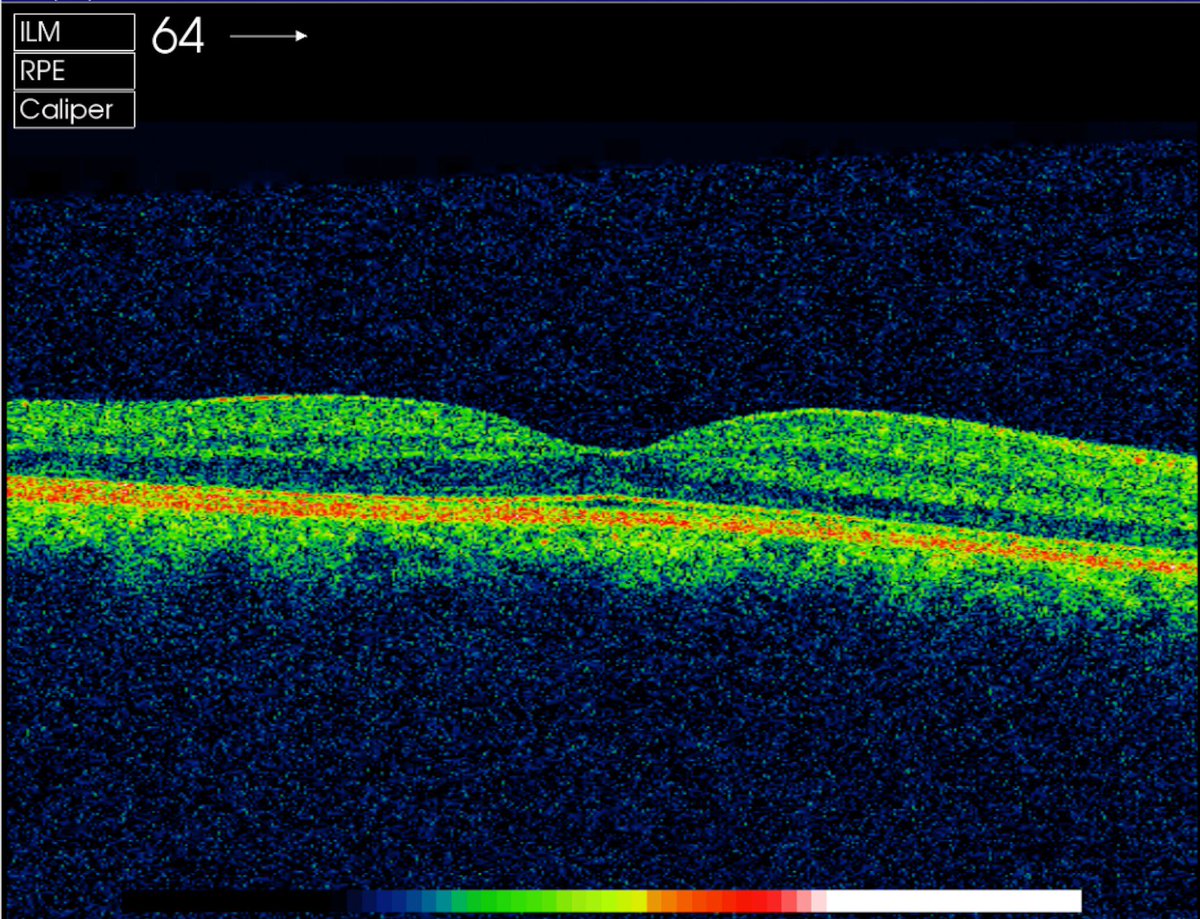

Vertical hyperreflective lesions seen on OCT images of patients with vitreoretinal lymphoma.https://ja.ma/2N7c54J

Optical coherence tomography was compared to fundus photos, fluorescein angiography, and light micrographs to examine Coats' diseasehttps://ja.ma/2N7c40F

Retweeted from Eric Topol: Will your eye OCT exams be a window to cognitive decline in the future? https://jamanetwork.com/journals/jamaneurology/fullarticle/2685869 …